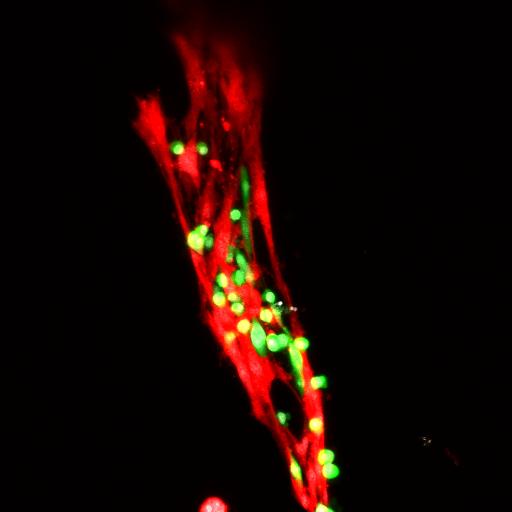

"Muscle satellite cells are resident stem cells in your skeletal muscles. They live on muscle strands like specks, and they're key players in making new muscle tissue," Han said.

Researchers at the Georgia Institute of Technology engineered a molecular matrix, a hydrogel, to deliver muscle stem cells called muscle satellite cells (MuSCs) directly to injured muscle tissue in patients whose muscles don't regenerate well. In lab experiments on mice, the hydrogel successfully delivered MuSCs to injured, aged muscle tissue and boosted the healing process while protecting the stem cells from harsh immune reactions.

"Our new hydrogel protects the stem cells, which multiply and thrive inside the matrix. The gel is applied to injured muscle, and the cells engraft onto the tissues and help them heal," said Woojin Han, a postdoctoral researcher in Georgia Tech's School of Mechanical Engineering and the paper's first author.

"The stem cells keep multiplying and thriving in the gel after it is applied," Jang said. "Then the hydrogel degrades and leaves behind the cells engrafted onto muscle tissue the way natural stem cells usually would be."